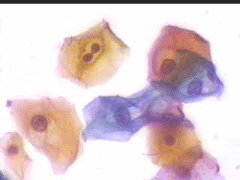

Κυτταρολογικές ατυπίες ερπητικής αιτιολογίας στο επίχρισμα κατά Papanicolaou, είναι σχετικά σπάνιο τυχαίο ευρημα σε ασυπτωματικές γυναίκες , ή εύρημα που εμφανίζεται σε περιστατικά υποτροπών συμπτωματολογίας κολπίτιδας..

Από πλευράς διαφορικής διάγνωσης παρουσιάζει ενδιαφέρον, επειδή μπορεί να συνυπάρχει με κυτταρολογικές αλλοιώσεις προσβολής από HPV, ή να συγχέεται με αυτές. Πρακάτω παρουσιάζουμε μία περίπτωση γυναικός, που παρακολουθήσαμε επί 13 χρόνια..

6.9.2002 Μετά από πάροδο διετίας επανέρχεται για προληπτικό έλεγχο.. Στο ιστορικό μικρο-υποτροπές κολπίτιδας, που ξεπερνούσε παροδικά με 3ήμερη χρήση Daktarin vag. supp. Το κολποσκοπικο εύρημα ήταν φυσιολογικό, ωστόσο το κυτταρολογικό επίχρισμα εμφάνιζε την τυπική πολυμορφία ερπητικών αλλοιώσεων.

4.8.2005 σε 2-3 οπτικά πεδία κυτταρολογικές ατυπίες που συνηγορούν για ερπητικές αλλοιώσεις ..

Στις 27.4.2010 εκ νέου σποραδική διακριτική κοιλοκυτταρική ατυπία και χαρακτηριστικές ατυπίες πυρηνων, που συνηγορούν, σε συνάρτηση με το ιστορικό, για ερπητικές αλλοιώσεις.